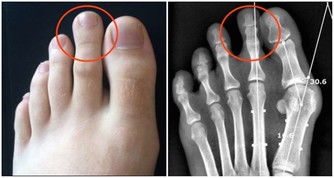

皮膚瘙癢、飯量變大、體重變輕:糖尿病

皮膚瘙癢同時伴有多飲、多尿、多食和消瘦的症狀,則可能是糖尿病導致的瘙癢。

數據顯示,約有10%的早期糖尿病患者會出現全身性或局部性的皮膚瘙癢,尤其在腋窩及腹股溝的部位最嚴重。